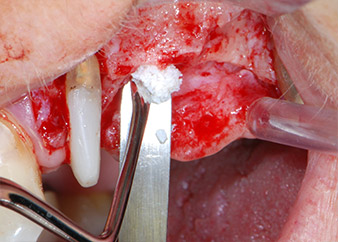

Преди поставянето на имплант, и последвалото потвърждение за непокътната Шнайдерова мембрана (Фиг. 9), вътрешният синус е повдигнат и в двете места на имплантите с помощта на ксеногенен костозаместващ материал (Bio-Oss, Geistlich Biomaterials) (Фиг. 10).

Фиг. 10: Поставяне на ксеногенен костозаместващ материал в имплантологичната остеотомия за вътрешна синусна аугментация. Материалът е внимателно кондензиран в апикална посока със сферичната CPITN сонда (не е показано).